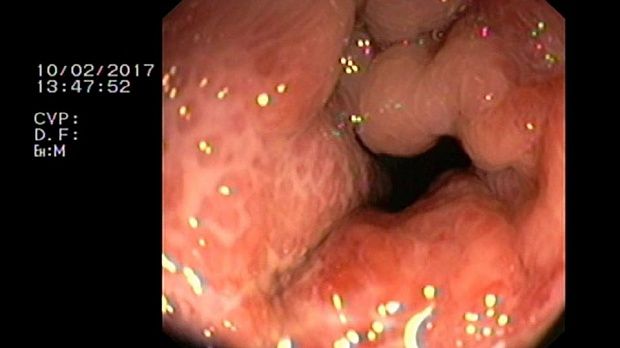

- Атлас